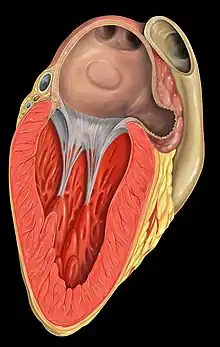

The atrium (Latin: ātrium, lit. 'entry hall'; pl.: atria) is one of the two upper chambers in the heart that receives blood from the circulatory system. The blood in the atria is pumped into the heart ventricles through the atrioventricular mitral and tricuspid heart valves.

There are two atria in the human heart – the left atrium receives blood from the pulmonary circulation, and the right atrium receives blood from the venae cavae of the systemic circulation. During the cardiac cycle the atria receive blood while relaxed in diastole, then contract in systole to move blood to the ventricles. Each atrium is roughly cube-shaped except for an ear-shaped projection called an atrial appendage, previously known as an auricle. All animals with a closed circulatory system have at least one atrium.

Humans have a four-chambered heart consisting of the right and left atrium, and the right and left ventricle. The atria are the two upper chambers which pump blood to the two lower ventricles.

The right atrium and ventricle are often referred to together as the right heart, and the left atrium and ventricle as the left heart. As the atria do not have valves at their inlets[2] a venous pulsation is normal, and can be detected in the jugular vein as the jugular venous pressure.[3][4] Internally, there are the rough pectinate muscles, and the crista terminalis of His, which act as a boundary inside the atrium and the smooth-walled part of the right atrium, the sinus venarum, which are derived from the sinus venosus. The sinus venarum is the adult remnant of the sinus venosus and it surrounds the openings of the venae cavae and the coronary sinus. [5] Attached to each atrium is an atrial appendage.

Right atrium

The right atrium receives and holds deoxygenated blood from the superior vena cava, inferior vena cava, anterior cardiac veins, smallest cardiac veins and the coronary sinus, which it then sends down to the right ventricle through the tricuspid valve, which in turn sends it to the pulmonary artery for pulmonary circulation.

Right atrial appendage

The right atrial appendage (lat: Auricula atrii dextra) is located at the front upper surface of the right atrium. Looking from the front, the right atrial appendage appears wedge-shaped or triangular. Its base surrounds the superior vena cava.[6] The right atrial appendage is a pouch-like extension of the right atrium and is covered by a trabecula network of pectinate muscles. The interatrial septum separates the right atrium from the left atrium; this is marked by a depression in the right atrium – the fossa ovalis. The atria are depolarised by calcium.[6]

Left atrium

The left atrium receives the oxygenated blood from the left and right pulmonary veins, which it pumps to the left ventricle (through the mitral valve (left atrioventricular valve) for pumping out through the aorta for systemic circulation.[7][8]

Left atrial appendage

High in the upper part of the left atrium is a muscular ear-shaped pouch – the left atrial appendage (lat: Auricula atrii sinistra). This appears to "function as a decompression chamber during left ventricular systole and during other periods when left atrial pressure is high".[9] It also modulates intravascular volume by secreting natriuretic peptides, namely atrial natriuretic peptide (ANP), and brain natriuretic peptide (BNP) into the coronary sinus, where they enter into the blood circulation.[10]

The left atrial appendage can be seen on a standard posteroanterior X-ray, where the lower level of the left hilum becomes concave.[11] It can also be seen clearly using transesophageal echocardiography.[12] The left atrial appendage can serve as an approach for mitral valve surgery.[13] The body of the left atrial appendage is anterior to the left atrium and parallel to the left pulmonary veins. The left pulmonary artery passes posterosuperiorly and is separated from the atrial appendage by the transverse sinus.[14] With certain conditions such as atrial fibrillation,[10] the left atrial appendage may be associated with risks of stroke from blood clot formation, because of which surgeons may choose to close it during open-heart surgery, using a left atrial appendage occlusion procedure.[15]